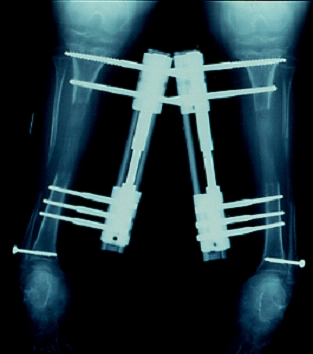

延長術後の経過